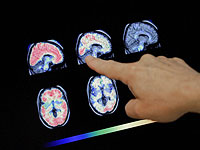

Недавние данные показывают, что с возрастом мужской мозг может сокращаться быстрее, чем женский. МРТ-сканирование 4726 человек с нормальными когнитивными способностями выявило "небольшие, но устойчивые различия между полами" в скорости утраты нервной ткани.

Международная команда ученых проанализировала более 12 000 снимков мозга, собранных за годы наблюдений у людей в возрасте от 17 до 95 лет. Каждый участник проходил как минимум два МРТ-обследования с интервалом примерно в три года. С учетом естественных различий в размере мозга между мужчинами и женщинами исследователи обнаружили, что у мужчин в пожилом возрасте ухудшения затрагивали большее количество областей мозга, включая обширные участки коры. У женщин же возрастные изменения наблюдались в меньшем числе зон, а толщина коры уменьшалась значительно медленнее. Ученые считают, что полученные данные указывают на существование реальных биологических различий в процессе старения у мужчин и женщин. Однако они подчеркивают, что выводы следует делать осторожно – для подтверждения результатов нужны дополнительные исследования.